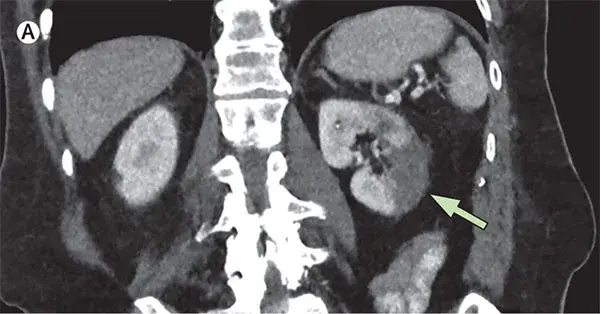

Uma causa incomum de hematúria glomerular intermitente!